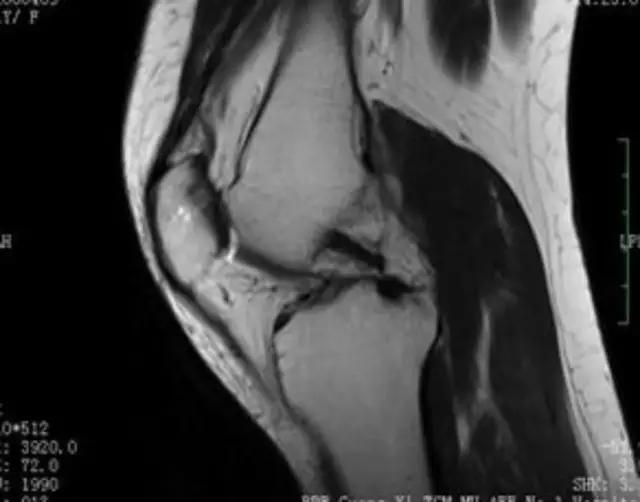

下图是同一个病人的MRI照片,MRI显示的内容更多,包括骨与软组织等,很多早期的、细微的病变都能清晰显示,其诊断报告对病人造成的影响也更大!

地中海贫血与白血病均为血液系统的问题,主要表现在骨髓,疾病的发病机理有别,MRI表现也不相同;我们可能不是很熟悉这些疾病,也能够从MRI发现区别。图1:正常膝关节 图2:地中海贫血 图3:白血病

我们可能都不熟悉T1、T2,怎么办?当我们发现有问题后,利用照片上图像的对比,推测病变的可能也是一种诊断方法。病例:黄XX,女,39岁,左膝关节反复交锁1年。图1:肿物信号与骨信号一样图2:肿物信号与骨信号一样图3:肿物信号与骨信号不一样 肿物应该与骨相关,但不是骨性,推断:膝关节滑膜软骨瘤。手术后得到证实。